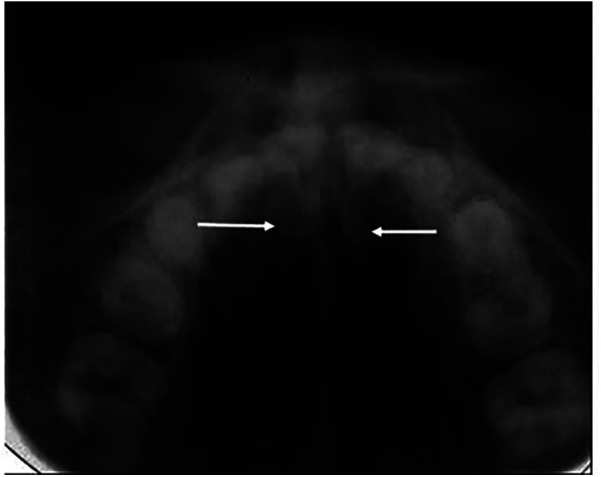

Results: The initial search yielded 4,864 citations, subsequently examined and supplemented by a hand search to find additional studies. Commonly used techniques for the localization of supernumerary teeth are the horizontal tube shift technique, vertical tube shift technique, vertex occlusal technique, and cone-beam computerized tomography.

Conclusion: The most commonly used localization techniques for supernumerary teeth are horizontal tube shift, vertex occlusal, vertical tube shift, and cone-beam computerized tomography. Conventional radiographs only provide two-dimensional views of 3-dimensional structures. Three-dimensional imaging alone can provide accurate data on impacted supernumerary teeth but, the need for this film has to be justified because of the higher radiation exposure.